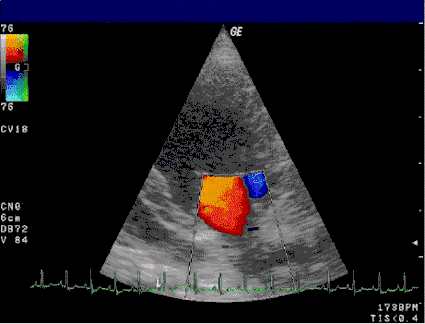

La ecocardiografía (eco) es el método más útil en el diagnóstico del prolapso de la válvula mitral. Las ecocardiografías bi- y tridimensionales son particularmente valiosas por permitir la visualización de las valvas mitrales en relación con el anillo mitral. Ello permite medir el grosor de la valva y su desplazamiento en relación con el anillo mitral. Un grosor de las valvas >5 mm y un desplazamiento >2mm es indicativo de un prolapso de la válvula mitral clásico. Permite también visualizar cualquier grado de calcificación del anillo mitral, la integridad de las cuerdas tendinosas y la localización detallada de anormalidades morfológicas en la válvula.[36]

Un eco Modo-M puede dar valores falsamente negativos así como falsamente positivos,[36] pero pueden mostrar prolapsos de 2 mm a media sístole y movimientos de las valvas al final de la sístole.[16]

El advenimiento del Doppler a la ecocardiografía permite ahora añadir un elemento funcional a las descripciones anatómicas del eco, el cual es útil en el diagnóstico de regurgitación mitral. El mapeo a color del flujo sanguíneo trans-mitral muestra la dirección, la velocidad y la cantidad del chorro regurgitante, si existe.[36]